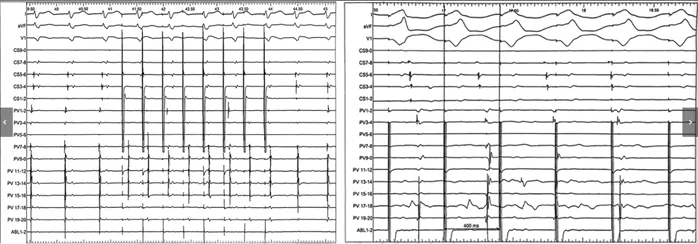

窄QRS波心动过速的心电图显示V-V、A-A、V-A及A-V间期均不规律,未见固定模式(图5)。心房超速起搏(S1S1刺激)未能终止该心动过速(图6左图)。心室起搏呈现室房分离现象(图6右图),据此可排除典型房室结折返性心动过速及室性心动过速。心动过速期间未维持1:1室房关系,可排除顺向型房室折返性心动过速。诊断倾向于多源性房性心动过速,但由于激动顺序复杂多变,标测难度较大。

图5 间期不规律的心动过速

图注:红线标示A-A间期,蓝线标示V-V间期。图中PV导联代表位于右心耳内的标测电极

图6 心房起搏未终止及心室起搏显示室房分离

图注:左图显示心房起搏,右图显示心室起搏